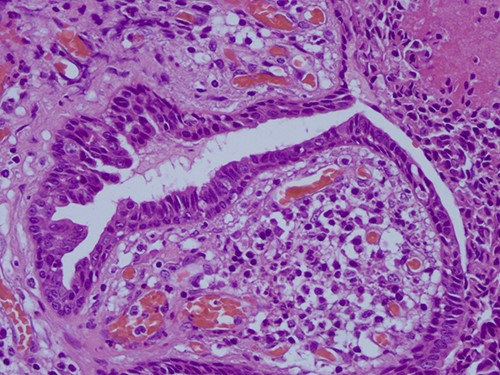

The histopathological examination found cystic invaginations of the infundibular epithelium projecting into the dermis, covered by a double cell layer (Fig. 2), proliferation of glands with prominent papillary architecture (Fig. 3) and fibrous cores containing numerous stromal plasma cells (Fig. 4). Other findings include verrucous (papillomatous) epidermal hyperplasia with hyperkeratosis and hypergranulosis (Fig. 5), irregular duct-like structures and cystic spaces (Fig. 6) and glands with double layer of cuboidal columnar epithelium and numerous stromal plasma cells (Fig. 7). These findings are compatible with Syringocystadenoma papilliferum with no signs of malignancy.

H&E staining 40× magnification. Fibrous cores of papillae contain numerous plasma cells and are lined by a double layer of cuboidal columnar epithelium.